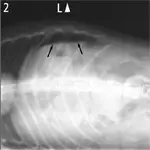

Figure 1. Crescent and triangular areas of free intraperitoneal gas (arrows) are shown that do not correspond to the tubular-shaped pattern of gas seen in the small intestine.(A) Lateral view, above. (B) Ventrodorsal view

A radiograph shows a lateral view of a dog's thorax, highlighting the presence of two arrows indicating a potential abnormality in the mediastinal region. The image captures the outline of the ribs and diaphragm, with a clear view of the heart and lungs.